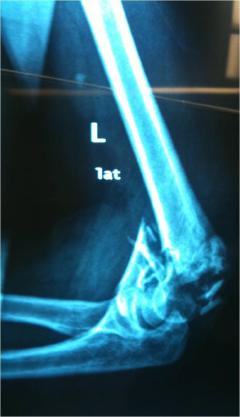

Περίπτωση 1ου ασθενούς

Προεγχειρητική